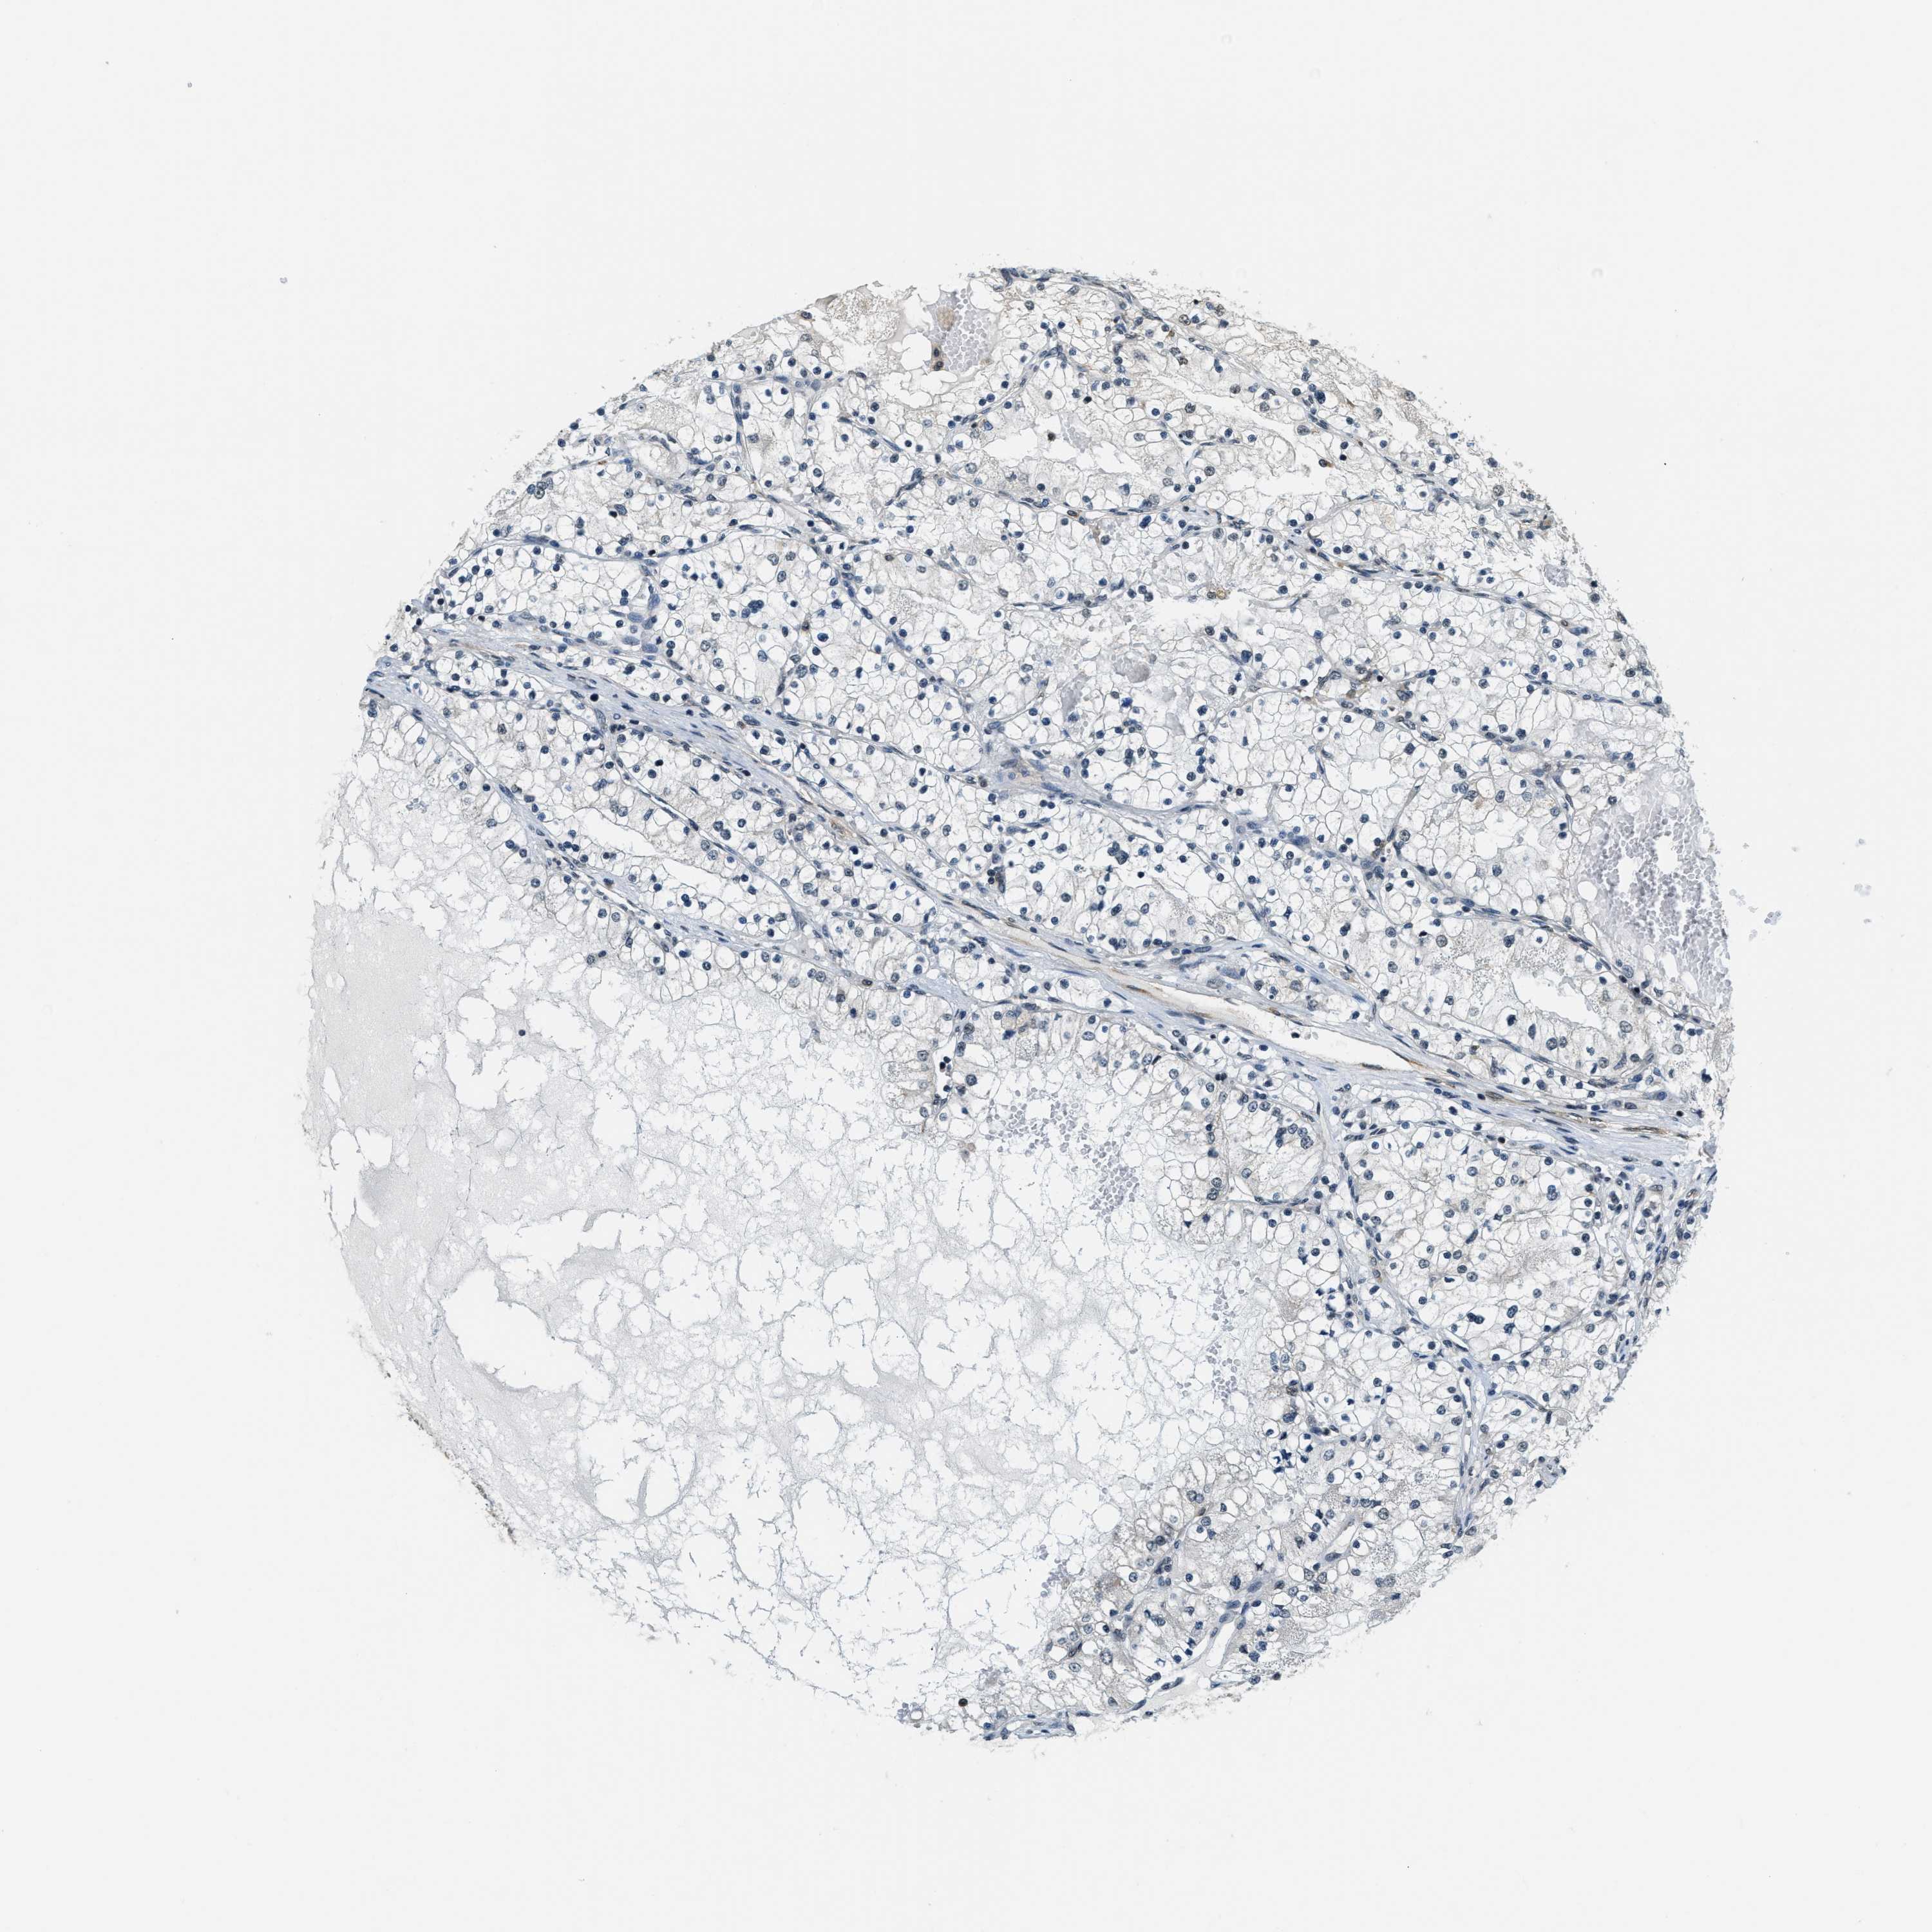

CANCER RENAL CANCER Show tissue menu

KICH TCGA KIRC TCGA KIRC VALIDATION KIRP TCGA PROTEIN RCC CPTAC PROTEIN EXPRESSION

Kidney renal clear cell carcinoma